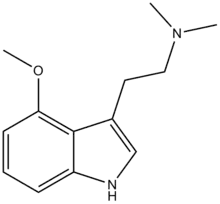

| 4-MeO-DMT | artificial | 4-OCH3 | CH3 | CH3 | 4-methoxy-N,N-dimethyltryptamine | 3965-97-7 |